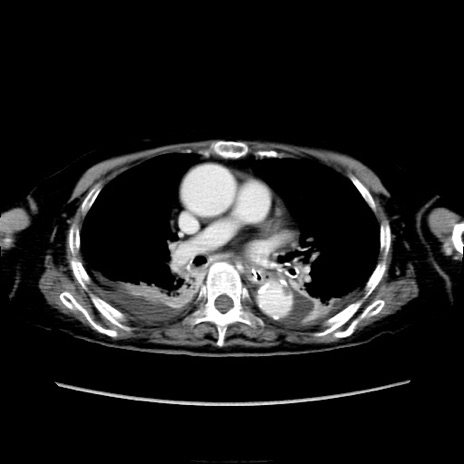

冠状断像

他院CT